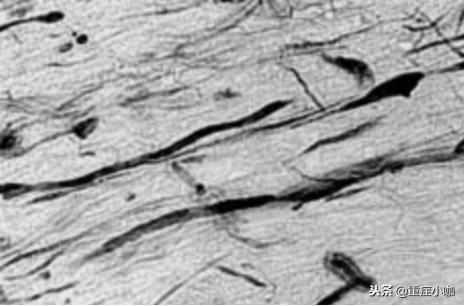

轴缩球(axonal retraction ball) 是 DAI光镜下诊断依据。轴索球是由轴索断裂后近端轴浆溢出膨大所致。

轴索球

轴索扭曲肿胀断裂